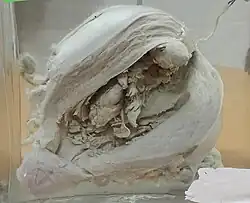

A histopatologia dos cancros do endométrio é altamente diversa. O que é encontrado mais comummente é um adenocarcinoma endometrioide bem diferenciado,[45] que é composto por numerosas glândulas pequenas e aglomeradas com vários graus de atipia nuclear, actividade mitótica e estratificação. Isso geralmente aparece no plano de fundo da hiperplasia endometrial. O adenocarcinoma Frank pode ser distinguido da hiperplasia atípica pela descoberta de invasão estromal clara, ou glândulas "costas com costas" que representam a substituição não destrutiva do estroma endometrial pelo cancro. Com a progressão da doença, o miométrio é infiltrado.[55]